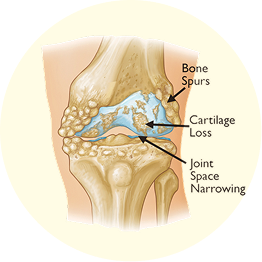

Knee pain often stems from osteoarthritis, where joint cartilage wears down over time, causing stiffness, swelling, and discomfort, especially after activity or rest.